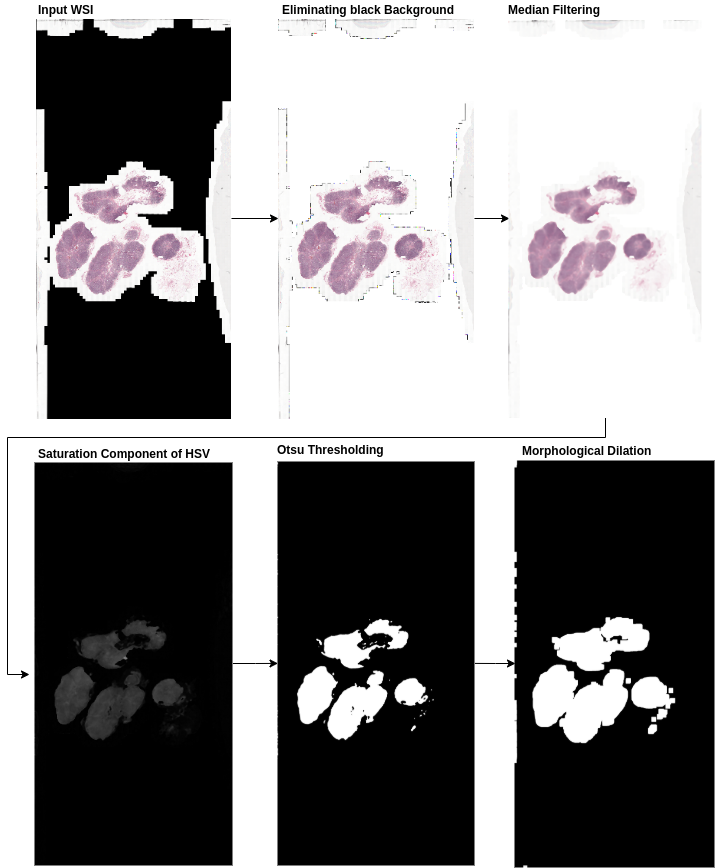

In this step, the entire tissue region was segmented from the background glass region of the whole slide image. This step aided in preventing unnecessary computations on non-tissue regions of the slide. An approximate tissue region boundary suffices, therefore the processing was done on a low resolution version of the whole slide image to further reduce computational costs. The RGB colour space of the low-resolution image was transformed to HSV (Hue-Saturation-Value) colour space and Otsu’s adaptive thresholding (Otsu, 1979) was applied to the saturation component. Post thresholding, binary morphological operations were performed to facilitate proper extraction of patches at the small tissue regions and tissue borders.

3.3.2 Tissue mask generation specific to CAMELYON dataset

In some of the CAMELYON17 cases, the Otsu’s thresholding failed because of the black regions in the whole slide image. Hence, before the application of image thresholding operation, the pre-processing involved replacing black pixel regions in the whole slide image back-ground with white pixels and median blurring with a kernel of size 7x7 on the entire image. Median blur aided in the smoothing of the tissue regions and removal of noise at the tissue bordering the glass-slide region while preserving the edges of the tissue. Figure 3 illustrates the pipeline for tissue mask generation with an example.